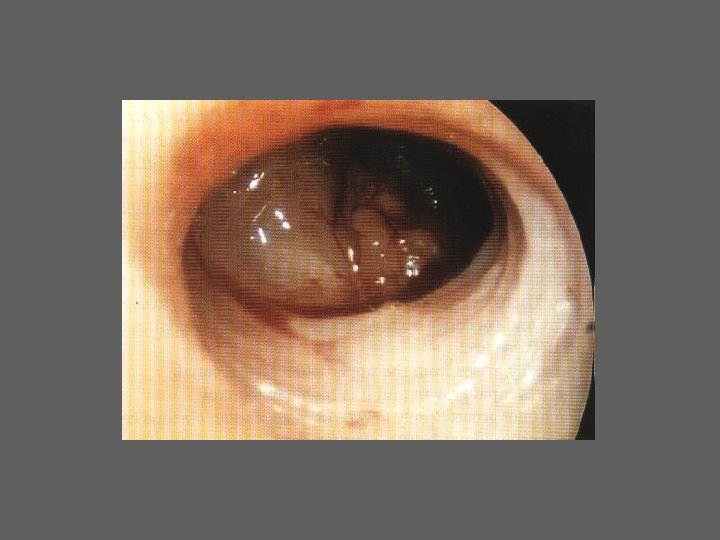

HISTEROSCOPIA - INDICAÇÕES Todas a situações em que se julgue vantajosa uma visualização completa da cavidade uterina, em particular: – Metrorragias – Dismenorreia adquirida – Infertilidade – Abortamentos de repetição e parto pré-termo – HSG anormal – DIU “perdido” – GIFT e ZIFT – Tratamento cirúrgico da patologia intracavitária: ● pólipos, miomas, septos, sinéquias, recessões endometriais ● baixos custos, reduzida morbilidade

HISTEROSCOPIA - MATERIAL CO 2 – Insuflador – Metrorragias max. 100 ml /min p < 100 mm Hg liquido (soro glicosado, dextrano, etc. ) – Fonte de luz fria – Histeroscópio (3, 5, 7 mm) – rígido ou flexível – Bainha e instrumentos cirúrgicos (pinça de biopsia, tesoura, etc.